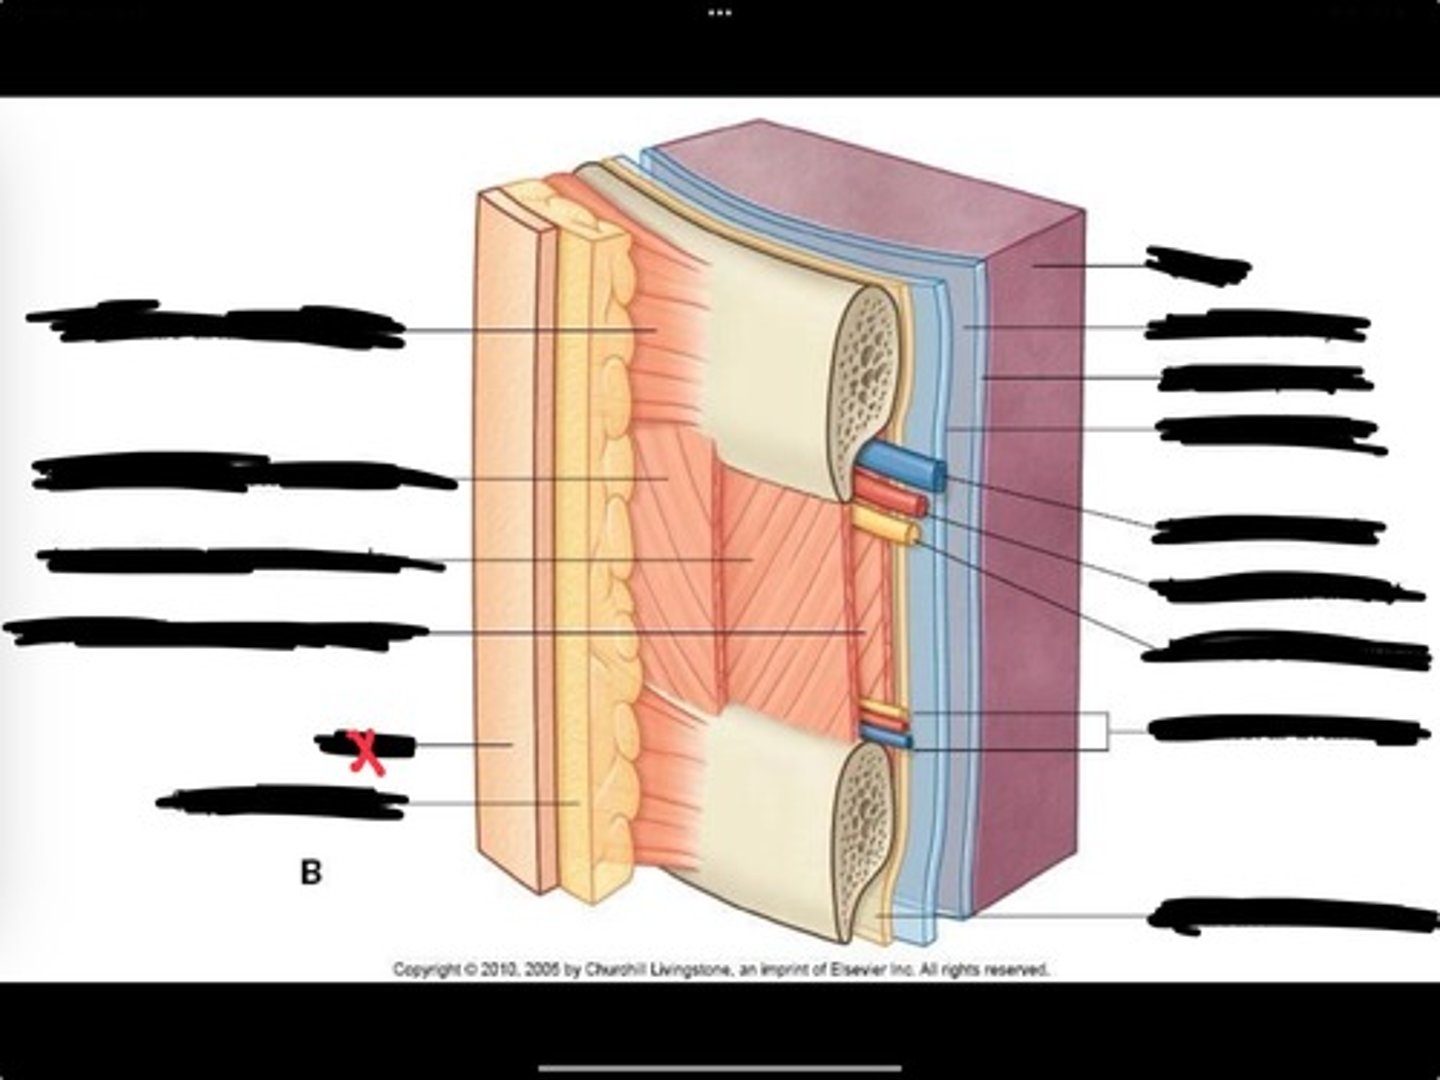

Innermost intercostal muscle

Skin

Internal intercostal muscle

External intercostal muscle

Serratus anterior muscle

Lung

Pleural cavity

Visceral pleura

Parietal cavity

Intercostal vein

Intercostal artery

Collateral branches

Intercostal nerve

Endothoracic fascia